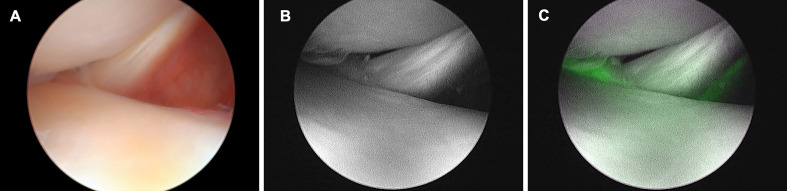

Objectives: This study aimed to use indocyanine green (ICG) fluorescence-guided knee arthroscopy to observe the meniscus and surrounding tissue vascularity and determine correlation with the patients' backgrounds. Currently, no data are available on the clinical application of ICG fluorescence-guided knee arthroscopy in assessing meniscal vascularity.

Main outcome measures: The times from ICG administration to fluorescence onset and fluorescence duration from onset to complete attenuation were recorded. The fluorescence intensity at the anterior, middle, and posterior segments of the meniscus was evaluated on a 4-point scale. The younger and older and smoker and non-smoker groups were compared.

Results: The average fluorescence onset time was 32.05 s, whereas the average fluorescence duration was 11 min 14 s. The age groups aged≤45 and ≥46 years showed an onset of 30±24.9 and 33.17±16.2 s and a duration of 12 min 54 s and 10 min 20 s, respectively. The smoking and non-smoking groups exhibited an onset of 28.33±14.4 and 33.84±21.5 s and a duration of 10 min 37 s and 11 min 32 s, respectively. All segments of the lateral meniscus showed higher fluorescence intensities than the medial. The posterior segment of the lateral meniscus at ≤45 was markedly more fluorescent and significantly different from ≥46.

Conclusions: Fluorescence was observed for approximately 30 s after intravenous ICG injection and lasted approximately 10 min. Fluorescence intensity was brighter in the posterior segment of the lateral meniscus, particularly at ≤45. ICG fluorescence-guided knee arthroscopy may assist in case-specific hemodynamics and real-time surgical evaluation of the meniscus in living humans.